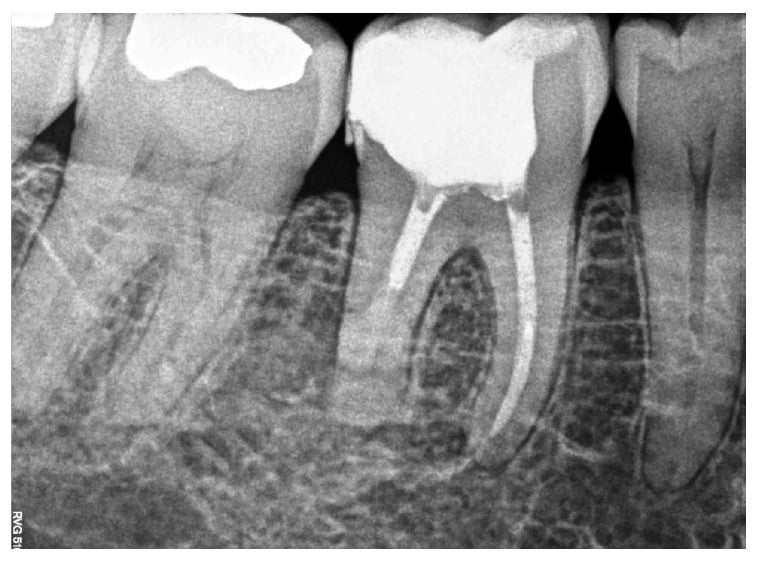

Patients typically need a root canal when there is inflammation or infection in the roots of a tooth. Symptoms may include severe pain, fever, swelling, an uneven bite (when you bite down, the treated tooth feels high), or you feel unwell. Open up (incise) and drain the abscess.

Web here are some common signs and symptoms of a root canal infection that mean you should schedule another visit to your dentist: Swollen gums is a symptom that is often associated with a root canal inflammation. A root canal infection, also known as endodontic infection, occurs when bacteria invade the innermost part of the tooth, known as the pulp, causing inflammation and potential damage to the surrounding tissues.